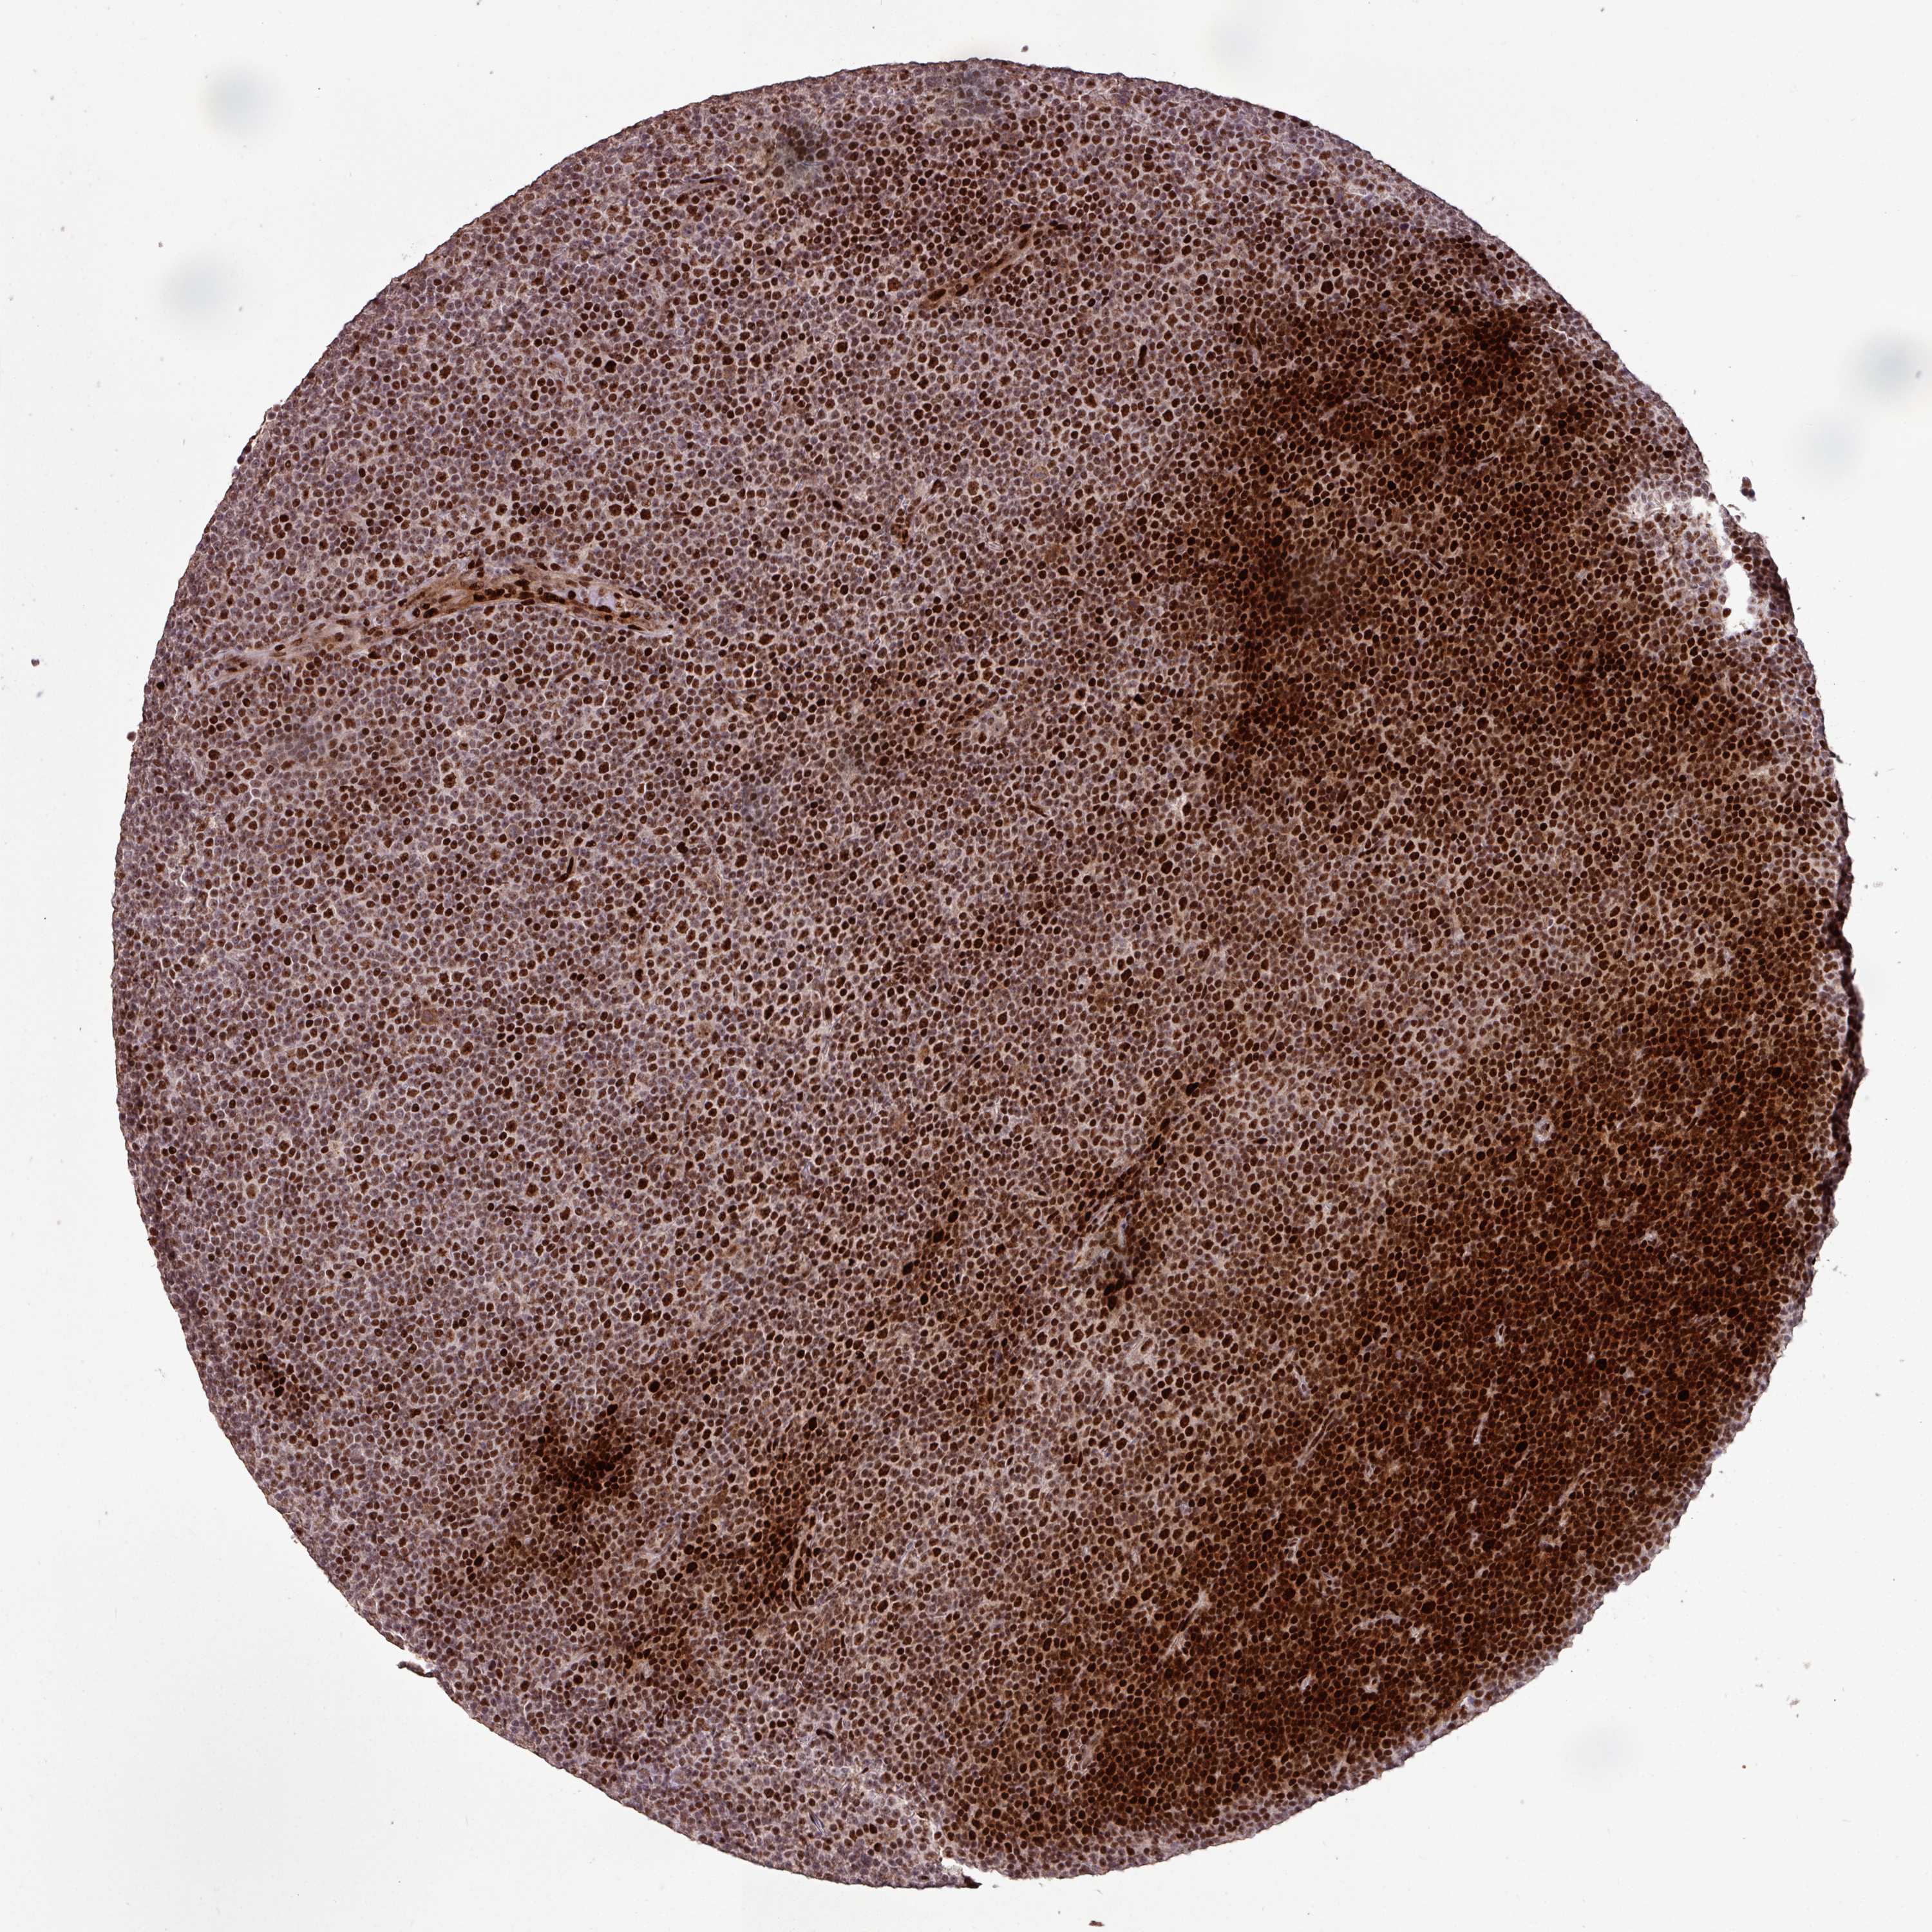

LYMPHOMA - Protein expressioni

A mouse-over function shows sample information and annotation data. Click on an image to view it in a full screen mode. Samples can be filtered based on level of antibody staining by selecting one or several of the following categories: high, medium, low and not detected. The assay and annotation is described here.

Antibody stainingi

Antibody staining in the annotated cell types in the current human tissue is reported as not detected, low, medium, or high, based on conventional immunohistochemistry profiling in selected tissues. This score is based on the combination of the staining intensity and fraction of stained cells.

Each image is clickable and will lead to virtual microscopy that enables deeper exploration of all samples and also displays staining intensity scores, fraction scores and subcellular localization as well as patient and tissue information for each sample.

Antibody HPA053153

Staining

High

Intensity

Strong

Quantity

>75%

Location

Nuclear

Hodgkin's disease, NOS

Malignant lymphoma, non-Hodgkin's type, High grade

Malignant lymphoma, non-Hodgkin's type, Low grade